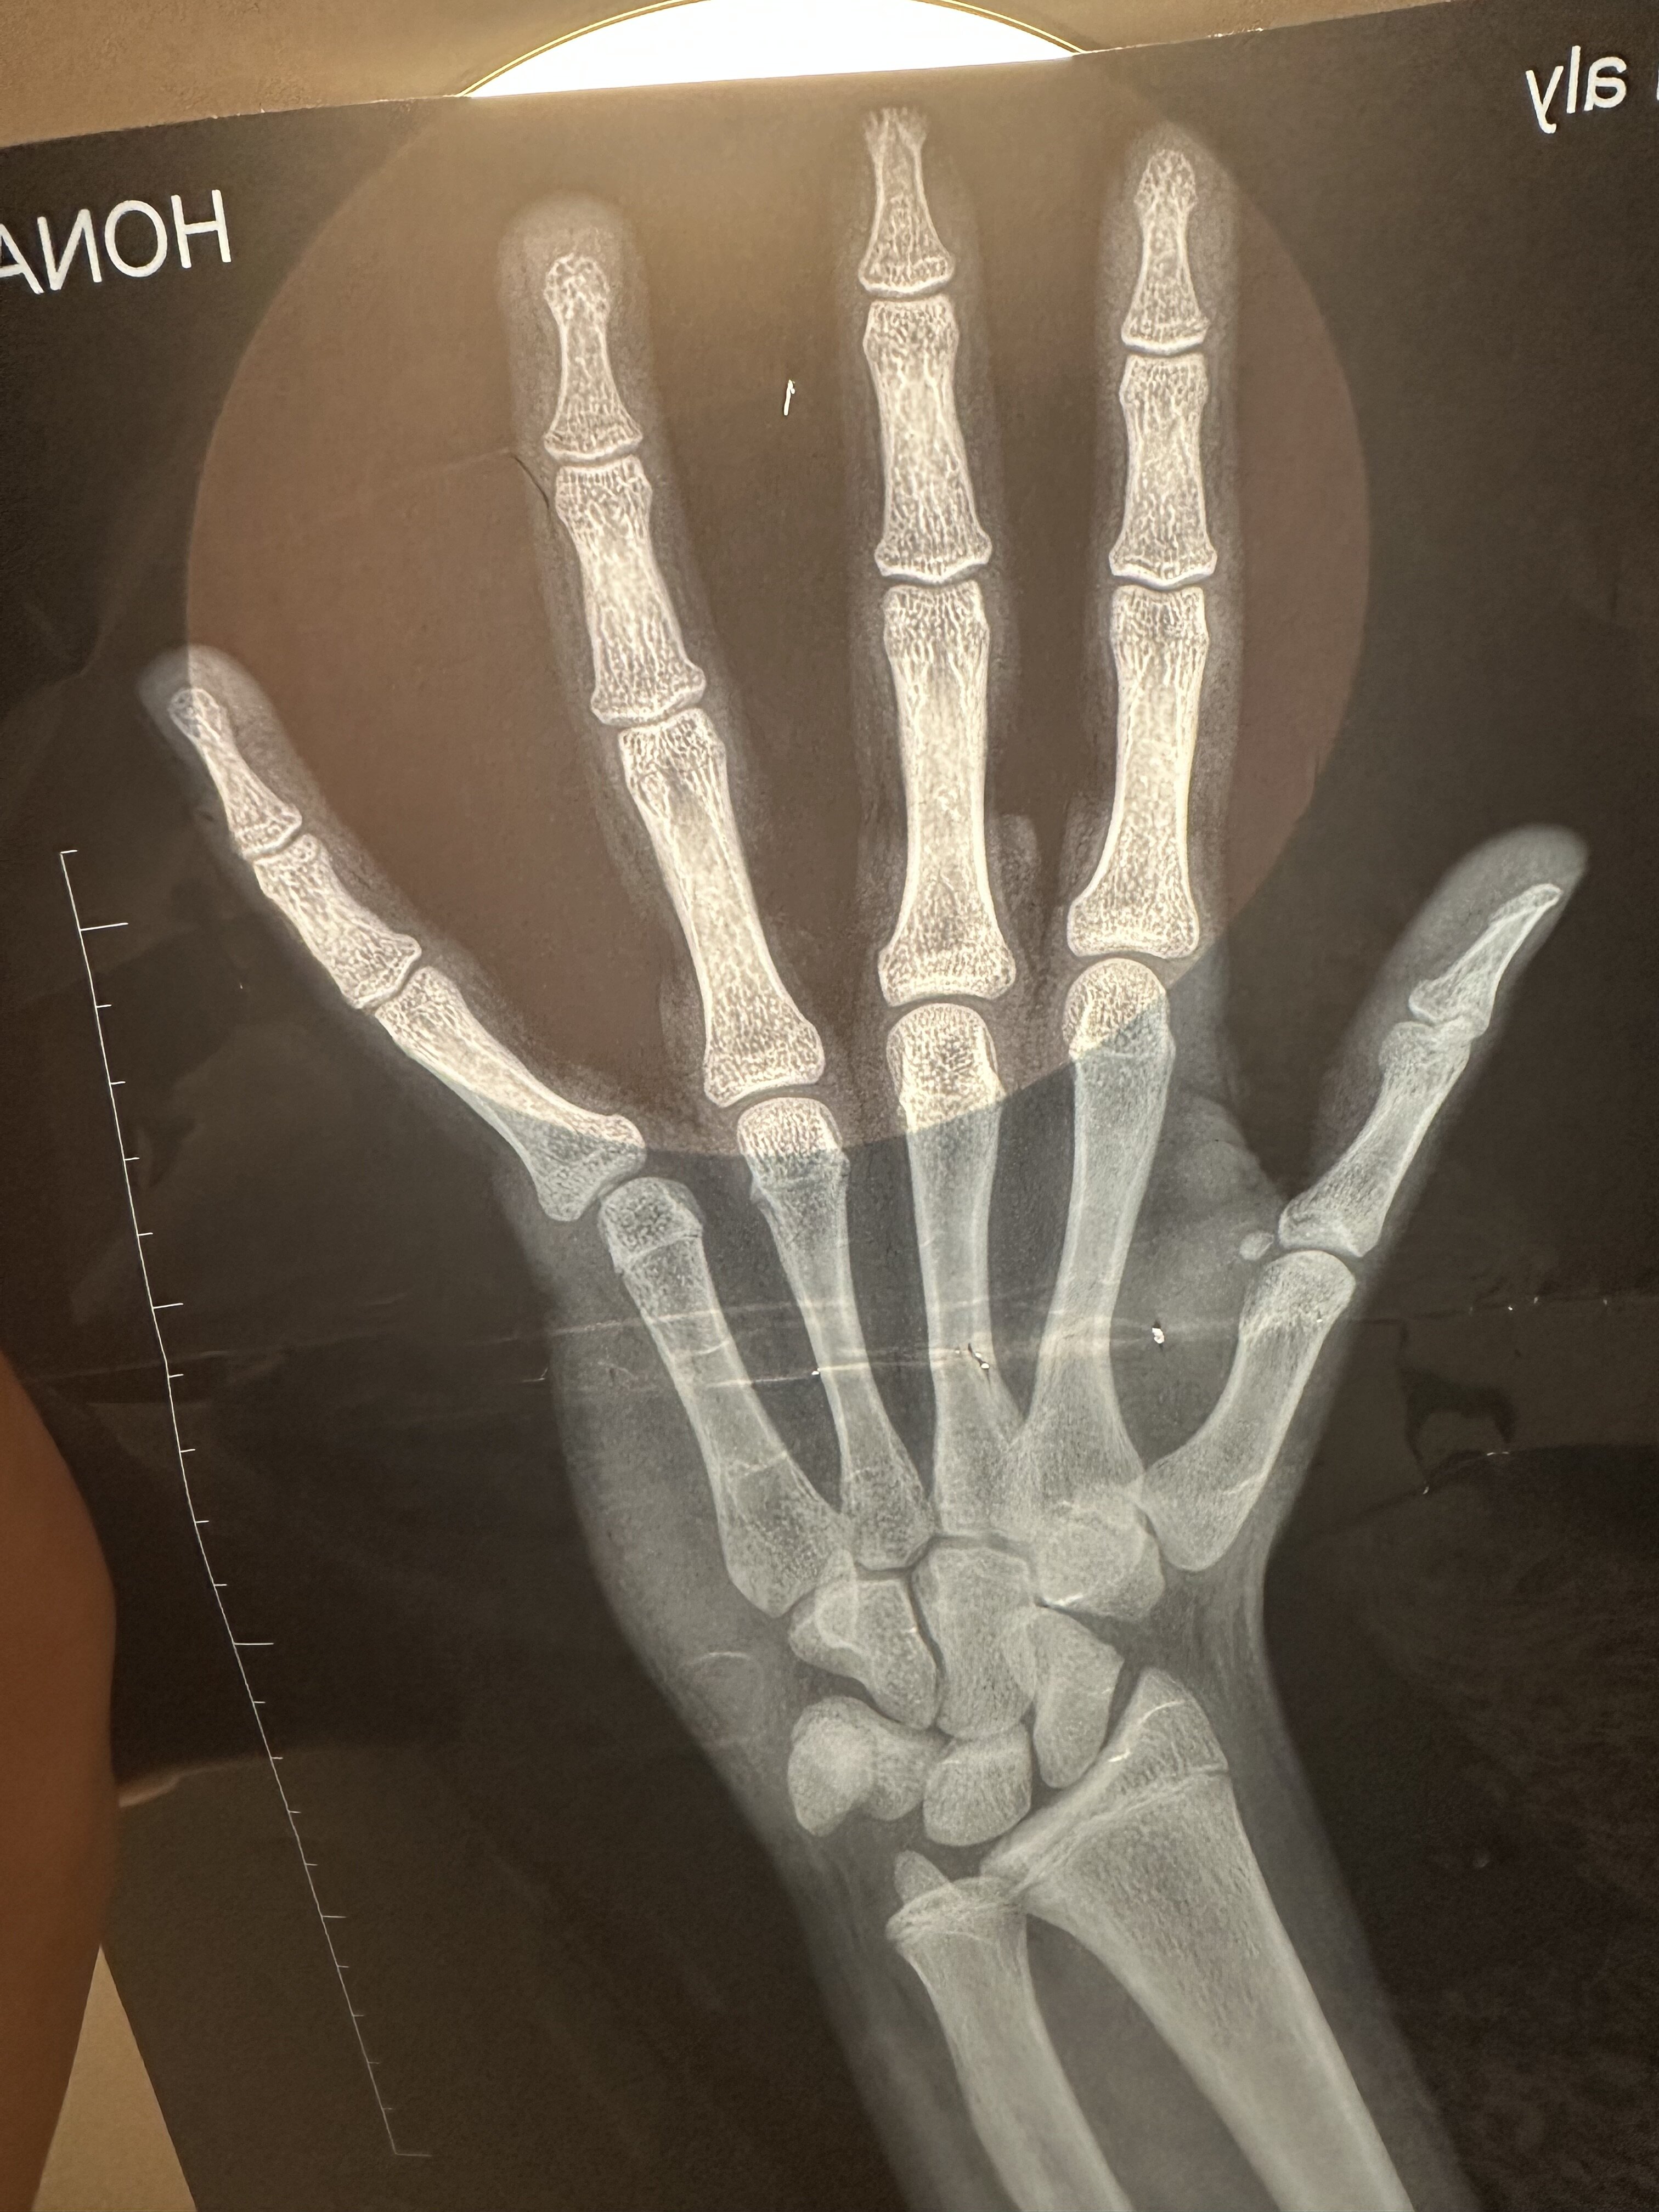

Is my growth plates closed am i cooked and if its not closed how many inches do i got left

They're still open, almost closed though

Can't accurately tell you how many inches you've got left just based on this xray